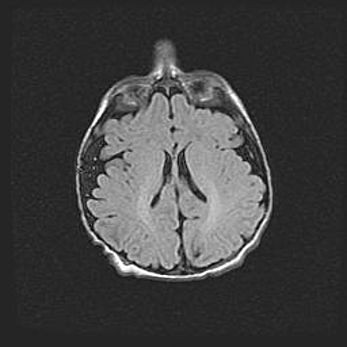

Лейкомаляция с кистозно-глиозной дегенерацией головного мозга.

Возраст: 2 месяца 25 дней

Вес: 6400 г

Окружность головы: 40 см

Срок гестации: 41 неделя

Лейкомаляцию относят к ишемически-гипоксическим повреждениям головного мозга, диагностируемым у новорожденных. При лейкомаляции в головном мозге обнаруживают очаги некроза, возникшие после тяжелой гипоксии и нарушения кровотока. В процессе морфогенеза очаги проходят три стадии: 1) развития некроза, 2) резорбции и 3) формирования глиозного рубца или кисты. Перивентрикулярная лейкомаляция (ПЛ) встречается примерно в 12% случаев среди новорожденных, обычно – у недоношенных детей, причем, частота ее зависит от массы, с которой младенец появился на свет. Наибольшее число малышей страдает лейкомаляцией, если масса при рождении 1500-2500 г.